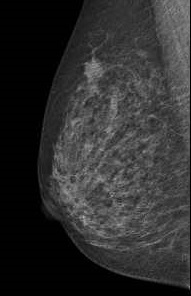

がん検診においても様々な画像診断が行われております。

胃がん検診にはバリウム製剤を使用した上部消化管検査、乳がん検診にはマンモグラフィー検査、肺がん検診には胸部X線検査やCT検査、全身のがん検診にはPET-CT検査などが行われています。最近ではMRI検査による乳がん検診も行われています。

マンモグラフィー画像